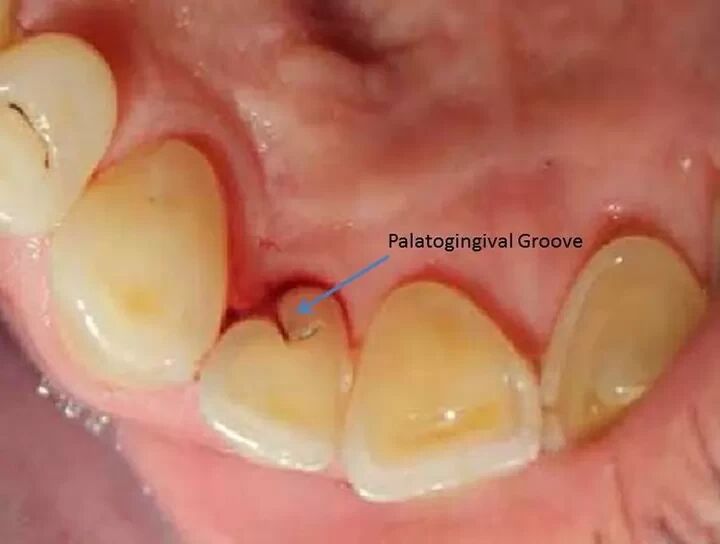

Palatal gingival groove(= Disto-palatal groove = Palatoradicular groove)

腭側齦溝 / 腭根溝

為牙根發育異常,容易造成牙周病與牙根吸收問題

補個圖片